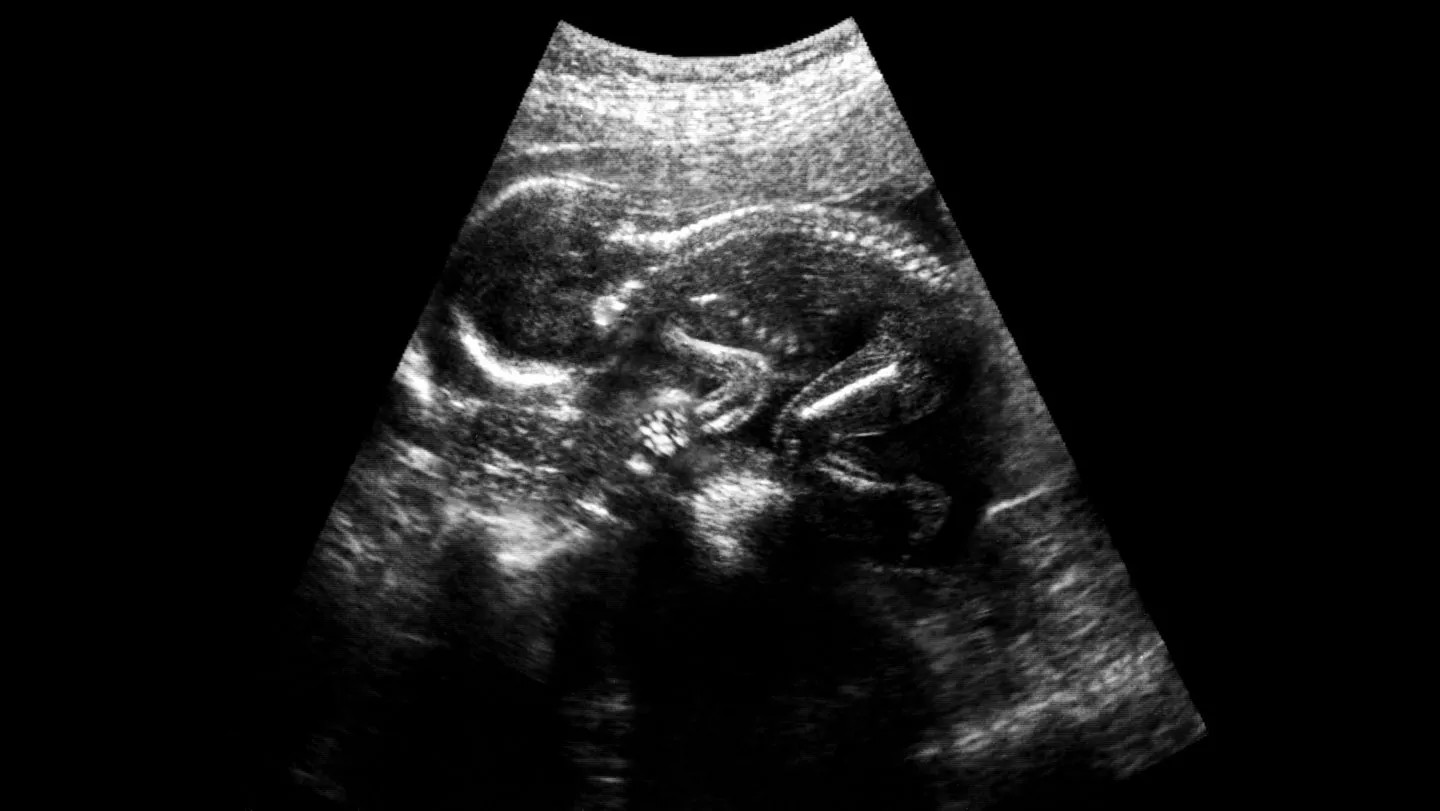

La espina bífida es un trastorno congénito en el que la columna vertebral no se cierra correctamente alrededor de la médula espinal. En el útero, esto deja el delicado tejido neural expuesto al líquido amniótico (que actúa como un irritante químico) y al trauma físico de las paredes uterinas.

Si bien los procedimientos de atención estándar actuales implican cirugía en el útero para cerrar quirúrgicamente la abertura de la columna, este método tiene una limitación importante: es una solución mecánica, no biológica.

Si bien la cirugía prenatal ha reducido con éxito la necesidad de derivaciones cerebrales y ha mejorado la capacidad para caminar, muchos niños todavía enfrentan parálisis de por vida y pérdida del control de la vejiga o los intestinos. El objetivo de esta nueva investigación es abordar la degradación nerviosa subyacente que se produce durante el embarazo.